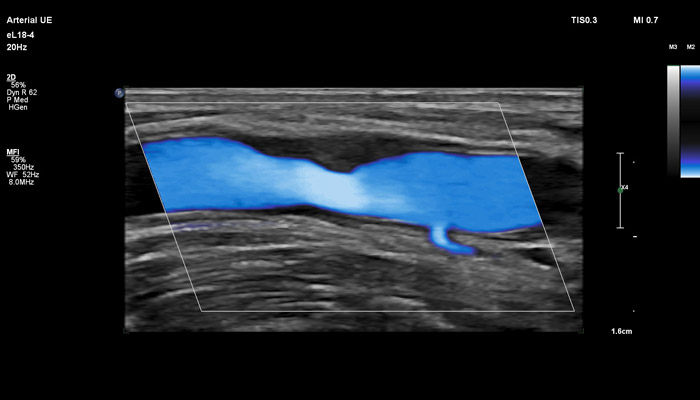

Инновационный датчик eL18-4 работает в частотном диапазоне 2-22МГц, что открывает широкий спектр возможностей его применения в ультразвуковой диагностике. Универсальность датчика позволяет использовать его для комплекса ультразвуковых исследований в таких областях, как: молочная железа (с функцией эластографии сдвиговой волной), поверхностные органы (с функцией эластографии сдвиговой волной), опорно-двигательный аппарат, исследования сосудов (с автоматическим измерением толщины сосудистой стенки), органы брюшной полости, исследования в педиатрии, пренатальная диагностика.

Линейный матричный датчик eL18-4 поддерживает режим высокочувствительной визуализации кровотока (Philips MicroFlow Imaging), новый запатентованный метод, который обеспечивает инновационный подход к оценке сосудистого русла. Визуализация MicroFlow преодолевает многие барьеры, связанные с традиционными методами обнаружения кровотока в малых сосудах, обеспечивая высокое разрешение при минимальных артефактах. Метод MicroFlow Imaging поддерживает высокую частоту кадров и качество изображения, применяет инновационные методы сокращения артефактов. Варианты вычитания 2D-изображений, смешивания и параллельного отображения обеспечивают превосходную визуализацию в различных клинических случаях.